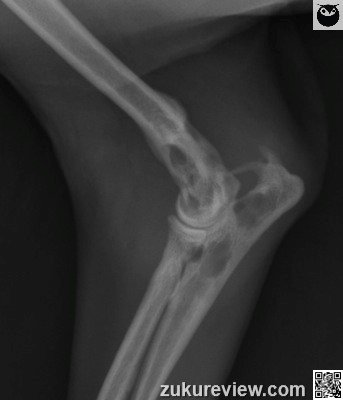

Radiographic interpretation: There is geographic lysis involving the distal humerus, proximal ulna, and to a lesser degree the proximal radius. The areas of bone loss are multifocal with relatively well circumscribed borders. The anconeal process is absent. There is a large soft tissue swelling centered around the left elbow.

Radiographic interpretation and images courtesy, Dr A. Zwingenberger and Veterinary Radiology. Normal radiograph links courtesy, Imaging Anatomy Univ. of Illinois Vet Med.